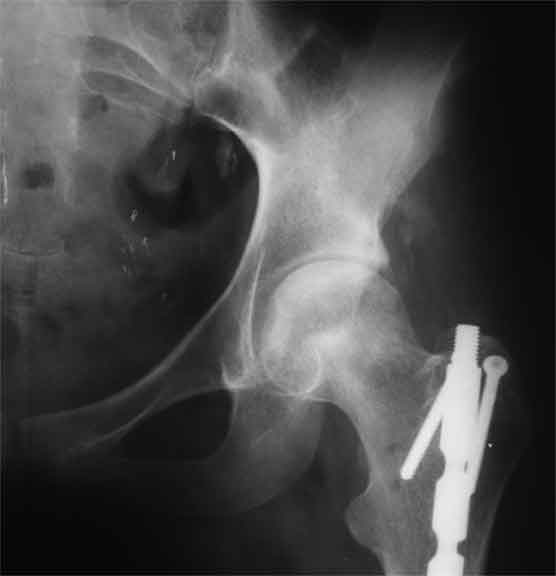

Насчет 8 см согласен с А.Н. Челноковым, это наверное ортопедическое за счет приводящей, сгибательной контрактуры и, возможно, колена. на ликвидацию укорочения у нас обычно уходит около 2-х нед. снимки в приложении, возможно не очень показательные, но других с ходу не нашел, завтра еще поищу.

Еще пара фото, ситуация несколько иная, задачи те же, открытое вправление застарелого вывиха в 2002, молодой возраст. Сейчас госпитализирована для эндопротезирования.